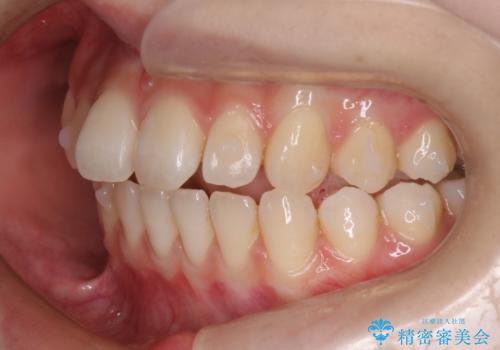

初診時の歯並びの状態としては、上下前歯が噛んでいない開口という状態であり、前歯を中心に上下とも歯の間に隙間がある状態でした。

抜歯は行わずマウスピース治療による主訴の改善を計画しました。